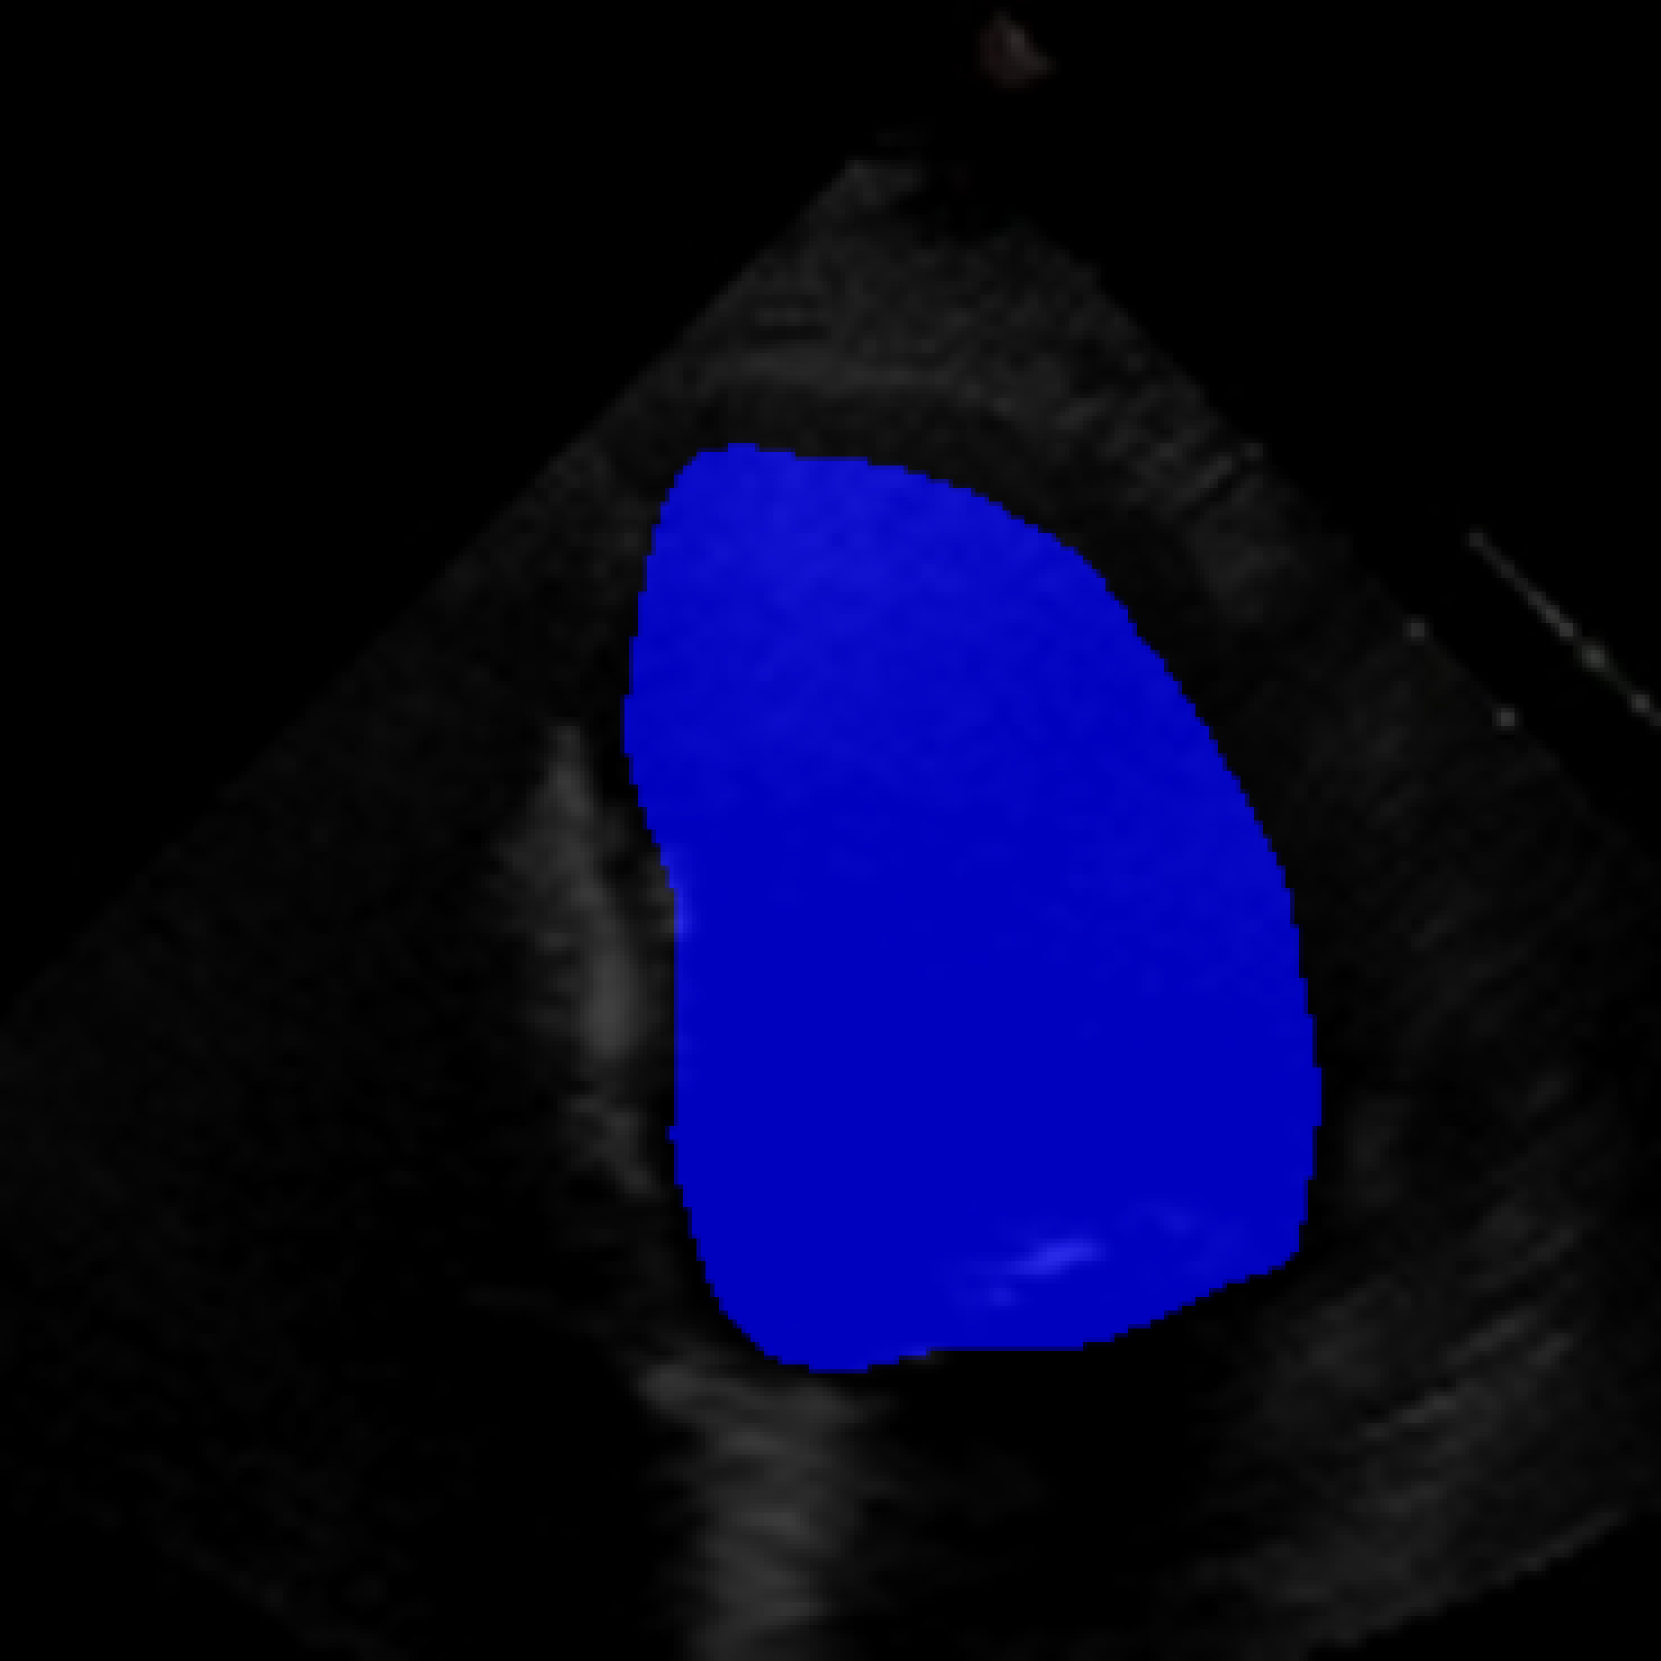

The 112x112 input is first resized to 299x299 as required by the Xception model. The Beat Extractor is then used to feed only whole beats to the LVEF estimation pipeline. A modified DeepLabV3+ model segments the left ventricle for every frame of the echocardiogram video (Figure LABEL:fig:segmentation). The area is measured, and a peak detector is then used to find the maximum (diastole) and minimum area (systole). The frame numbers corresponding to these extrema are recorded, and the video is clipped into smaller videos that go from diastole to systole. These smaller videos are independently fed to the Xception based feature extractor.

The ConFormer model demonstrated high performance in the estimation of Left Ventricular Ejection Fraction (LVEF) from echocardiogram videos (Figure 2). The model achieved a mean absolute error of 6.57 in LVEF prediction, indicating a high level of accuracy in its estimations (Table I). Notably, ConFormer outperforms the full video assessment of LVEF by EchoNet-Dynamic, a significant achievement given the model’s efficiency. With just 5.82 million parameters, ConFormer is significantly more efficient than existing models, making it a practical tool for real-world applications.